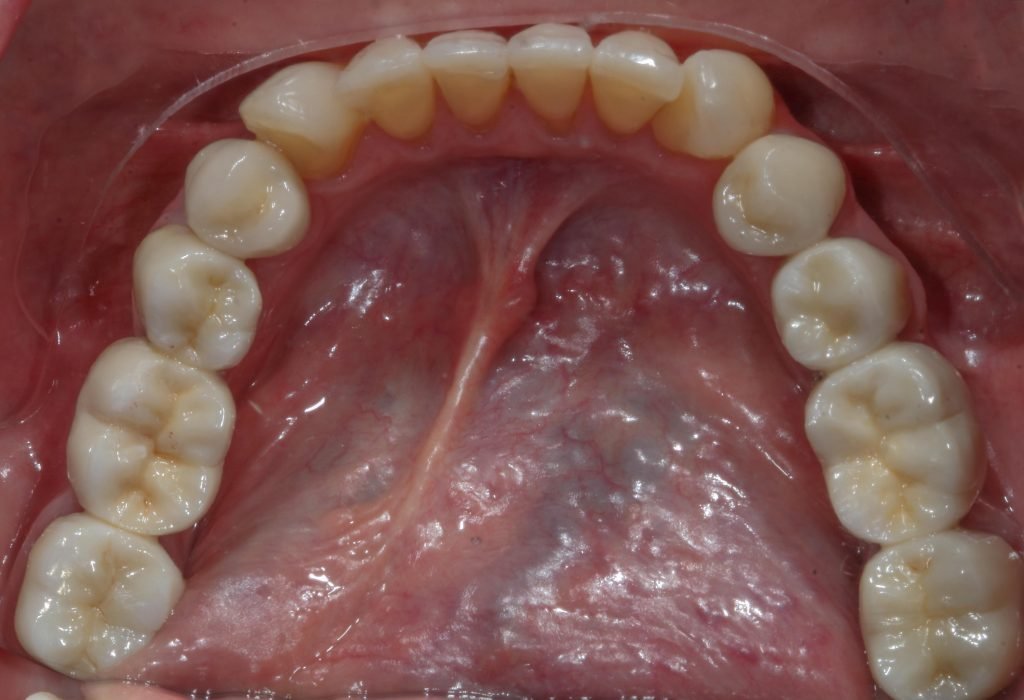

Punto Bajío Casos Clínicos Prótesis Fija sobre Implante unitario Inicio Provisional Final Prótesis Parcial Fija sobre 2 Implantes 2 Implantes Final Prótesis Bucal Removible Inicial Inicial Superior Inicial Inferior Rayos X Inicial Rayos X Inicial Frontal Final Final Superior Final Inferior Prótesis Parcial Fija/ Coronas de Circonio Sonrisa Inicial Foto Inicial Foto Inicial Inferior Foto Final Inferior Foto Final Sonrisa Final Prótesis Total Protesis Inmediatas 1 Protesis Inmediatas 2 Prótesis Removible/ Coronas Metal-Ceramica Carillas Incrustaciones Endodoncia